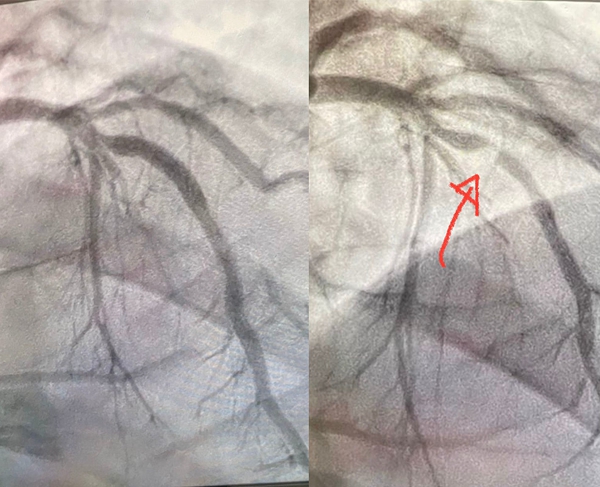

巴西CS:GO教练zews在心脏病发作后住院进行相关治疗,顺利出院后他在个人社交媒体上谈到了自己的健康状态。据他所说,自己曾被医生告知死亡概率超过90%,且留下永久性伤害的概率达95%以上。他的心脏动脉几乎完全阻塞,但医生专家们还是将zews从鬼门关中拉了回来。

zews在4月24日感到胸部和左臂疼痛,在前往医院的路上突发心肌梗塞,进入医院抢救后在第一时间进行了手术,他坚强的意志和医生精湛的技艺成功创造了一个奇迹。经过一段时间的治疗后,zews在5月5日顺利出院在家静养,他表示自己可能经历了人生中最为可怕的时刻,但在几天的恢复后将重新回归到自己的项目中进行工作。